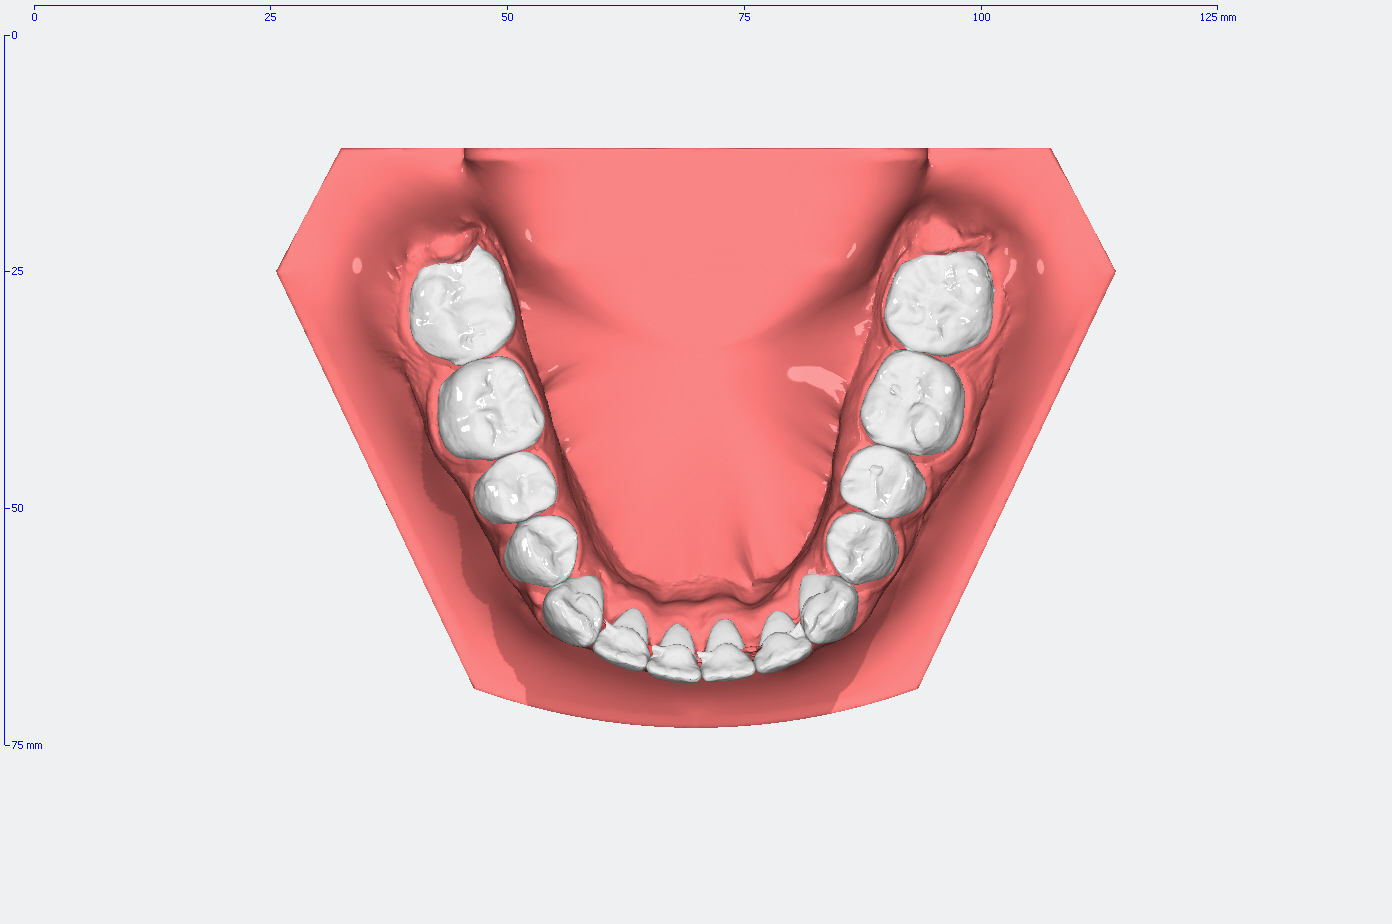

Die Entwicklung der Zahnstellung im Gebiß anhand von 3D Modellen

In den Abbildungen unten sehen Sie den Vergleich der Zahnstellung in den Gebissmodellen in der ursprünglichen Form und nach der kieferorthopädischen Behandlung.